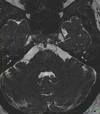

Ecchordosis Physaliphora

Cystic lesion in the prepontine cistern without enhancement or restricted diffusion extending into bone.

Absence of enhancement or restricted diffusion together with non-aggressive bony margins in this location is typical of a retroclival ecchordosis physaliphora, a notochord remnant.

Ecchordosis physaliphora is a congenital benign hamartomatous lesion derived from notochord remnants, usually located in the retroclival prepontine region, but can be found anywhere from the skull base to the sacrum.